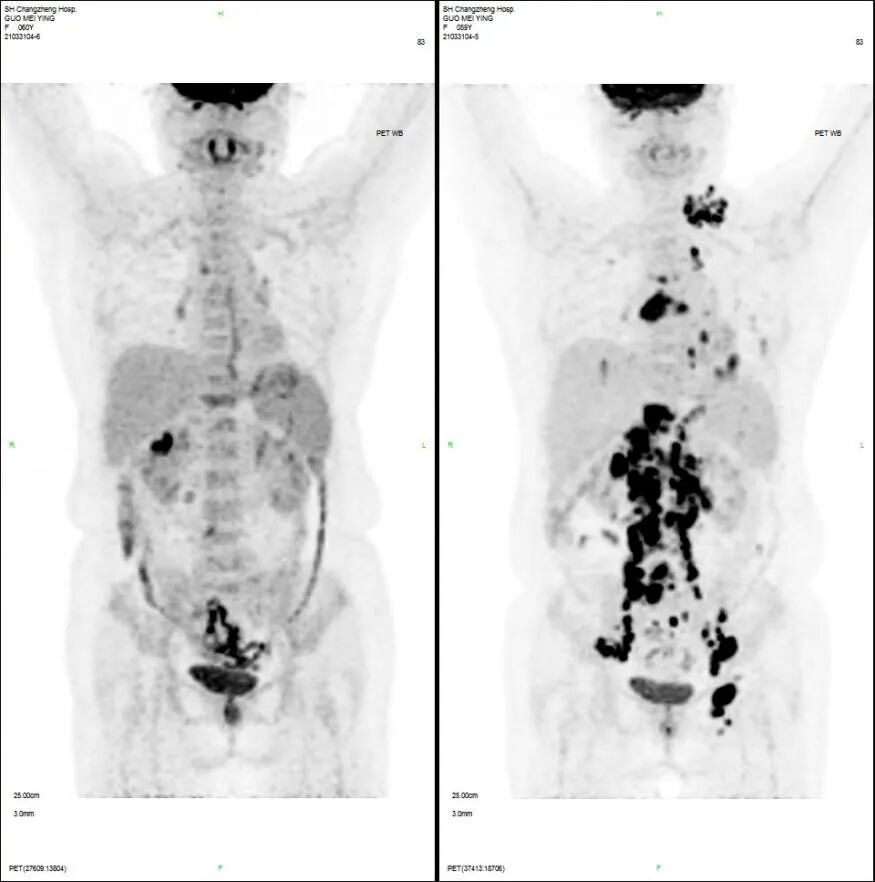

在全球,结直肠癌是发病率位居第三位、病死率位居第二位的肿瘤。肠镜筛查的普及以及手术方式的提升显著降低了结直肠癌的死亡率,但仍有一部分患者在初诊时已发展为晚期,失去手术根治的机会,且预后较差,5年生存率仅12%。许多转移性结直肠癌(mCRC)患者在经历一线治疗后,面临无药可用的困境。近年来,随着靶免联合治疗在系统治疗中逐渐前移,各种靶向治疗药物在mCRC的诊疗中也越发举足轻重。本文分享2例晚期结肠癌患者的诊疗经过,呈现瑞戈非尼在二线治疗为患者带来长生存的治疗价值及其良好的后线应用前景,以期为临床医生提供诊疗借鉴。 病例提供:海军军医大学附属长征医院 王湛 王湛 病例基本情况 一般信息:女 ,58岁。2020年10月,患者无明显诱因出现腹胀,无伴随症状,未予重视。后腹胀进行性加重,2020年11月中旬下腹部隐痛,与进食及体位变化无关,无肩背部放射痛。 辅助检查: 腹部超声:腹腔积液。 腹水脱落细胞病理:腺癌。 腹部增强CT:结肠肝曲癌;腹盆腔积液,腹盆腔腹膜多发转移。 结肠镜(2020-12-4):升结肠近肝曲见隆起型新生物,范围约4cm,新生物表面分叶状,质脆,触之易出血。肠腔狭窄,内镜尚可通过。 2020-12-8病理:横结肠,中分化腺癌,含部分粘液腺癌。 一线治疗2020-12-03至2021-02-24 CAPEOX+贝伐珠单抗 治疗4周期 病情进展,腹胀、腹痛加重,腹水增加。 2021-3-31 PET-CT:腹腔内及腹膜、脾脏、纵隔及右侧心膈角区、左侧锁骨区多发代谢增高灶,结合病史,考虑转移;双肺转移;腹腔及盆腔积液;结肠显示欠清,请结合肠镜检查;双侧胸腔少量积液,左肺下叶部分不张;双肺少许慢性炎症;右肝血管瘤;左肾结石。;子宫术后,痔疮可能;脊柱退变,腰3不稳,腰3/4、4/5、腰5/骶1椎间盘突出。 PFS:3个月 2021-4-6,完善基因检测(腹水标本):KRAS/APC/TERT/TP53/ target=_blank class=infotextkey>P53 突变,TMB 7.98/Mb,MSS 二线治疗,2021-04-02至2021-12 2021-3-31 2021-6-2 2021-8-6肠镜:结肠镜顺利插至回盲部,回盲瓣呈唇状。结直肠粘膜呈桔红色,光滑湿润,有光泽。血管纹理呈树枝状,清晰可见。 PFS:8月 三线治疗,2021-12-13至2022-01-23 三氧化二砷 2021-6-2 2021-11-22 2021-11-22 2022-2-8 PFS:2月 四线治疗,2022-02-10 化疗+免疫+瑞戈非尼+三氧化二砷 2022-2-10开始使用小剂量化疗(雷替曲塞+奥沙利铂+伊立替康)+免疫(信迪利单抗)+瑞戈非尼+三氧化二砷治疗。 疗效评估(2022-9-20):患者病情再次取得缓解。 2022-9-22至今采用维持治疗,降低治疗强度:雷替曲塞 +信迪利单抗+瑞戈非尼+三氧化二砷 2022-9-20 2023-2-8 PFS:13个月+ 该患者为中年女性,诊断为晚期多发转移性结肠癌,基因检测提示KRAS突变,BRAF、NRAS野生型,微卫星稳定,无法进行根治性切除。一线治疗加予CAPEOX联合贝伐珠单抗,治疗4周期后出现病情进展,腹胀、腹痛加重,腹腔积液增加,二线采用瑞戈非尼联合免疫和化疗,患者耐受良好,1周期后腹胀明显缓解,全身状态、PET-CT、肠镜结果较之前明显改善,继续原方案治疗,PFS长达8月。二线治疗进展后完善基因检测,发现TP53 突变,经与患者充分沟通,三线治疗采用三氧化二砷,疗效不佳。四线治疗在三氧化二砷基础上加用瑞戈非尼+免疫+化疗,患者病情再次取得缓解,PFS 超过13个月。近年来,随着精准医学及靶向、免疫治疗的发展,mCRC的管理与治疗策略的制定也变得复杂,合理选择治疗手段、优化全程管理至关重要。本例患者经历了一线化疗联合免疫治疗后疾病出现快速进展,我们个体化地在二线治疗中应用瑞戈非尼联合方案,患者疾病得到控制,PFS 8个月。在四线治疗方案中,再次挑战瑞戈非尼,依然获得较好的疾病控制效果,目前PFS已超过13个月。基于CORRECT和CONCUR研究,瑞戈非尼用于mCRC三线治疗已积累大量临床数据,目前已成为mCRC三线标准治疗方案。此外,REGONIVO、REGOTORI以及RIN方案证实了瑞戈非尼联合免疫治疗MSS型肠癌取得更长的总生存期。一线治疗后疾病进展,能否将瑞戈非尼使用前移,在二线治疗中加用以进一步延长患者生存,以及前线已经暴露过瑞戈非尼,后线再次使用瑞戈非尼是否可行,仍待在临床研究中进一步证实。 02 病例分享二 病例提供:海军军医大学第一附属医院 王薇 王薇 病例基本情况 一般信息:男性,41岁。2020年10月8日,无明显诱因下出现便血,为鲜红色,伴肛门坠胀不适,无排便习惯改变,无腹胀,无消瘦。1997年因“胃溃疡”行胃部幽门切除术;2019年行混合痔手术。 辅助检查: CEA 3.4ng/ml,CA199 3.52u/ml。 当地医院肠镜(2020-11-20):(距肛缘8-10cm)可见粘膜不规则隆起,表面溃烂,易出血。 肠镜活检病理:(直肠)中分化腺癌。 盆腔MRI增强(2020-11-26):直肠中段癌,考虑mrT3N1Mx,MRF-,EMVI-。 肝脏MRI增强(2020-11-27):未见明显异常。 治疗经过 首次手术治疗2020-12-09 腹腔镜辅助直肠癌拖出式适形切除术+末端回肠造口术 术中探查:直肠下段肿物,质硬,未浸润浆膜层,周围系膜未见肿大淋巴结。肿瘤大小约4*4*2cm,占肠腔1/2周,系膜完整。 术后病理: 直肠溃疡型肿瘤大小4.5x3.5x1.5cm;中至低分化腺癌,部分为粘膜腺癌;浸润至外膜层; 癌结节( 3枚+)、脉管癌栓(+)、神经侵犯(+)、肿瘤出芽(+,PDC1级);上下切缘(-)、环周切缘(-)、吻合圈(-);周围淋巴结(2/6),直肠外膜淋巴结(2/4),最高群淋巴结(0/4); 基因分型:KRAS Exon-2 G12D突变,NRAS、BRAF、PIK3野生型;免疫组化:MSH2(+),MSH6(+),MLH1 (+),PMS2(+),pMMR;Ki-67 80%。 术后分期:pT3N2aMx IIIB期 术后辅助治疗(XELOX方案) XELOX方案化疗3周期; 拟行盆腔放疗50gy/25次,2021-03-25起放疗6次 术后复查 肝脏MRI增强(2021-03-27):肝脏多发结节,较前为新发,考虑肝内多发转移瘤 一线治疗,2021-04-22至2021-06-24 mXELIRI+贝伐珠单抗 治疗4周期 患者治疗后出现恶心呕吐,胃纳明显减退,Ⅱ°粒细胞下降,腹泻,脱发,轻度手足皮肤反应,手足冰凉,心悸。患者无法耐受继续治疗 维持治疗,2021-7-15至2021-8-26,卡培他滨+贝伐珠单抗,共计治疗3周期 肝脏MRI增强(2021-5-31、2021-8-24):肝右后叶上段7mm小结节灶,转移不除外,腹膜后稍大淋巴结较前相仿,随访。 2021-3-27与2021-5-31的肝脏MRI增强对比图 2021-8-24 肝脏MRI增强 盆腔MRI增强(2021-8-25):术区及骶前软组织肿胀,左侧条索影,结合CT考虑术区置管术后改变,较2021-06-01片大致相仿。 疗效评估:PR 后患者诉心悸、乏力、胃纳不佳;血压正常;心肌酶正常;心脏彩超LVEF 64%;EKG: 窦性心率,T波低平;尿蛋白(-)。患者对化疗非常抗拒。 二线治疗,2021-09-17至2021-12-15 盆腔MRI增强(2022-9-13):术区及骶前软组织肿胀,左侧条索影,结合CT考虑术区置管术后改变,较前片大致相仿。 胸部CT(2022-9-13): 右肺下小结节,随访。 疗效评估:PR。 2022-12-20肝脏MRI增强:平扫+增强未见明显异常。 2022-12-21盆腔MRI增强:直肠癌术后,盆腔区未见明显复发及转移病灶。 病例总结 该患者为中年男性,诊断为局部晚期直肠癌,原发灶术后分期IIIB期,基因检测KRASExon-2G12D突变、微卫星稳定。术后仅3月余在XELOX方案辅助化疗、盆腔放疗期间出现多发肝转移,疾病进展转移灶不可切除,进而接受XELIRI方案联合贝伐珠单抗二线全身治疗。治疗后肝脏多发转移瘤退缩理想,病灶明显缩小减少。但患者治疗副反应不可耐受,改卡培他滨联合贝伐单抗治疗后持续有效,但仍无法耐受副反应。遂予以瑞戈非尼靶向治疗:120mg日剂量口服,服用三周停用一周至今。患者耐受良好,近期复查未发现明显复发转移病灶。目前二线PFS已达23个月,瑞戈非尼二线维持治疗DoR17个月。目前,二线治疗在不同患者亚群的优选方案仍存在争议。而整个系统治疗到了三线阶段,标准治疗主要价值是能够延长患者的疾病控制时间,缩瘤效果和客观缓解率均不理想,并没有满足目前的治疗需求。根据目前的药物机制和临床研究结果,考虑到患者的具体情况:涵盖治疗目标、体质状况、对预估的不良事件的耐受性及是否存在相关危险因素、既往治疗用药情况等方面,我们采用了个体化的瑞戈非尼二线维持治疗方案取得良好疗效,这种治疗策略希望能在规范临床研究中证实。病例分享一